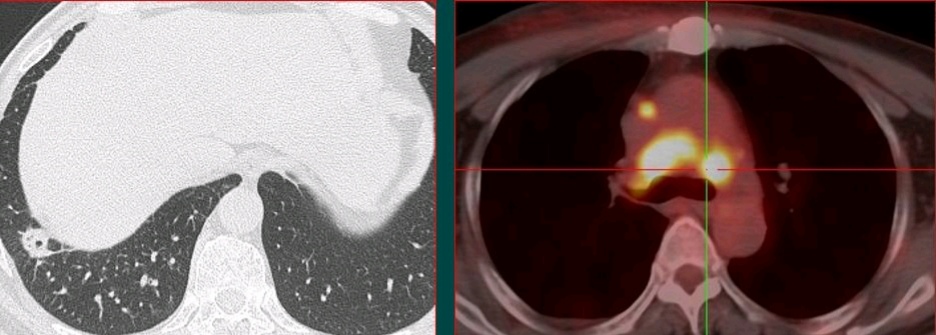

这个病例是豪大夫的师傅,山东肿瘤医院的黄教授提供

这位病人是一位78岁的老爷子,体检发现左肺不规则结节,有毛刺,有胸膜牵拉,高度怀疑肺癌。

但是增强扫描发现病灶没有任何强化,说明病灶没有供血血管,提示这是一个结核球(结核杆菌会破坏一切,形成局部干酪样坏死,没有血管所以增强扫描不强化;少数活动期病灶可以周边包膜样强化;极少数明显均匀强化)。

后来进一步穿刺证实为结核性肉芽肿,避免了挨一刀。